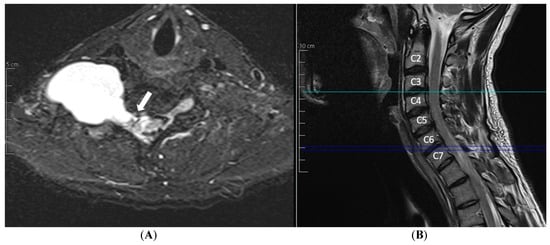

3. Case Report